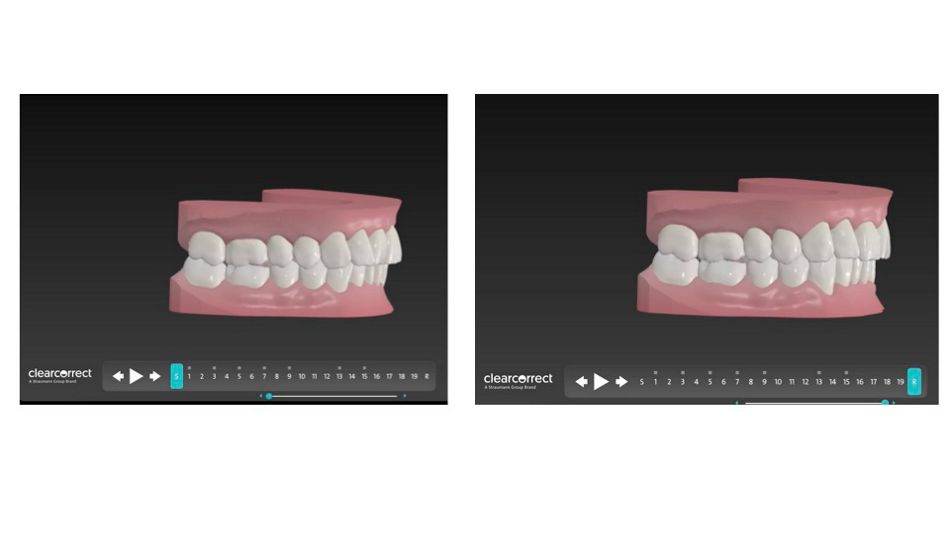

Zunächst einmal wurde der Patient mit dem TRIOS 4 Scanner intraoral gescannt. Es wurden 8 kieferorthopädische Fotos aufgenommen. Diese Daten wurden unter kieferorthopädischen, funktionalen und ästhetischen Aspekten analysiert [1,2,3,4] und in das ClearCorrect Portal hochgeladen, wo eine Fallplanung wenige Tage später vorgeschlagen wurde.

Das Hauptziel war es, die Oberkieferfront, die aufgrund des tertiären Engstandes retrudiert war, wieder aufzurichten, sowie durch die Retrusion und Intrusion der Unterkieferfront, soviel Overjet zu schaffen, dass der Unterkiefer durch Autorotation in eine bequemere Position gelangen kann. Gleichzeitig wurde durch bukkalen Wurzeltorque der oberen Prämolaren, der Oberkiefer leicht expandiert, um einen ästhetischen Bukkalkorridor zu erlangen und dem Unterkiefer etwas mehr Platz in der Transversalen zu gewähren [4].

Die ersten Aligner wurden eingesetzt. Es waren insgesamt 19 Aligner Sets für die erste Phase der Behandlung vorgesehen. ASR wurde in Höhe von 2,4mm im Unterkiefer appliziert, um genug Overjet durch Retrusion der Unterkieferfront zu gewährleisten und gleichzeitig den Frontzahnengstand zu beheben. Der Oberkiefer benötigte nicht mehr als 0,5mm ASR. Es wurden vertikale Attachments auf 14, 13, 21, 24, 25, 33, 31, 32 angebracht, um Rotationen und bukkalen Wurzeltorque der Incisivi und Prämolaren zu ermöglichen, wodurch der Zahnbogen wieder als Ganzes aufgerichtet werden sollte. Es wurde nur ein horizontales Attachment auf 31 appliziert, um dessen Intrusion zu erleichtern.

Nach 19 Aligner Stufen, wurden alle bisherigen Attachments entfernt und für die Revision gescannt, um etwas mehr Overjet zu schaffen. Weitere 11 Aligner Sets wurden geplant und vom Patienten getragen. Um Zahn 11 körperlich besser bewegen zu können, wurde ein 3 x 1 mm horizontales Attachment angebracht. Weitere 0,9mm ASR wurden im Unterkiefer durchgeführt, um die Unterkieferfront weiter zu retrudieren. Im Oberkiefer wurde lediglich zwischen Zahn 11,21 0,3mm ASR appliziert, um das verbleibende schwarze Dreieck zu schließen. Die Revision sollte nie als Fehlversagen eingeordnet werden, sondern vielmehr als Möglichkeit ein hundertprozentiges kieferorthopädisches Ergebnis für den Behandler und Patienten zu erreichen.

Schon während der Initialphase der Behandlung merkte der Patient an, dass sich sein Biss schon viel besser anfühle. Durch das seitliche Anheben des Bisses, um 1,52mm aufgrund der okklusalen Sperrung der Aligner, verspürte der Patient sofortige Erleichterung. Nach der Revision hatte der Patient eine perfekte Envelope of Function und die drei goldenen Regeln der Okklusion, wie von J.L.Ruiz [8] beschrieben, sind im vollen Umfange umgesetzt worden.

Fallplanung vorher und nachher hinsichtlich der Envelope of Function

Fallplanung vorher und nachher bezüglich der inzisalen Inklination und der daraus resultierenden restriktiven Envelope of Function und dessen Korrektur.